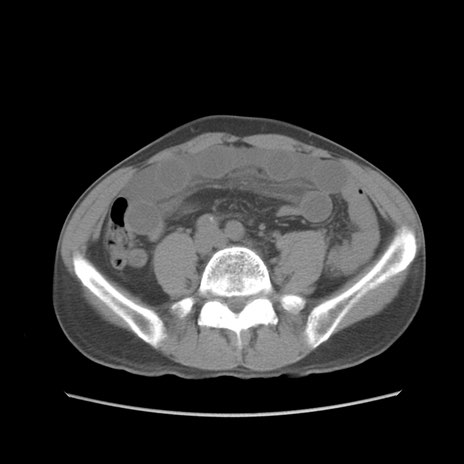

症例56 CT(横断像)

脂肪ウインドウ